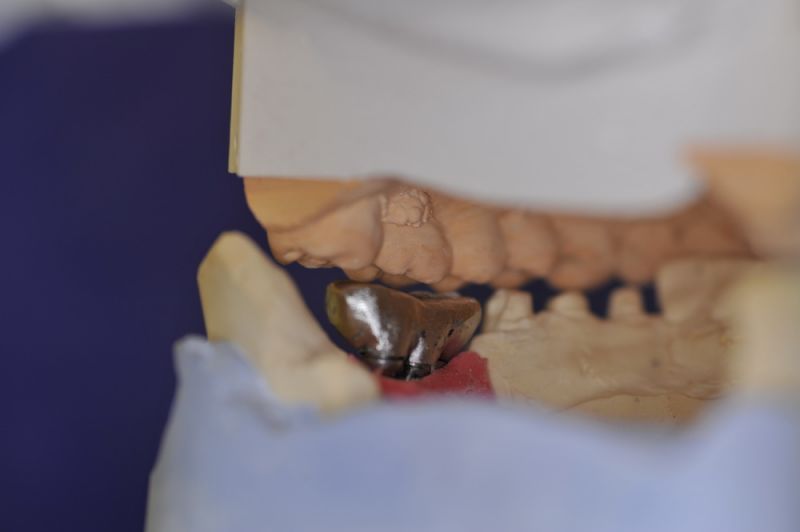

1. Notwendigkeit einer implantatgestützten Kronenversorgung mit der Vorgeschichte, dass die Patientin eine Vielzahl von Behandlern aufgesucht hatte, die eine Implantation im Unterkiefer als nicht durchführbar einschätzten.

2. Extrem schlechte knöcherne Verhältnisse im Unterkieferseitenzahnbereich, die sich intraoperativ noch einmal als ungünstiger darstellten, als bereits in den Voruntersuchungen erkennbar.

3. Sehr dünne Implantate, die von ursprünglich zwei je Kieferhälfte auf letztendlich drei je Kieferhälfte umgeplant werden mussten.